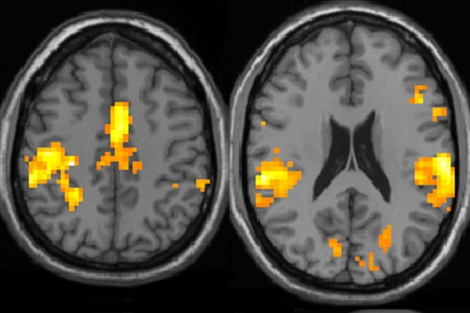

- Estos pacientes tienen más activas las áreas cerebrales asociadas al dolor

juegan los genes? ¿Cuál es el mejor tratamiento? Los estudios de imagen

funcional muestran que estos pacientes procesan de forma diferente el dolor. El

doctor Richard Gracely, del Centro de Investigación en Fatiga y Dolor Crónico

Georgetown (Washington, EEUU), fue el primero en demostrar que las áreas

involucradas en el procesamiento de los estímulos dolorosos son las mismas en

estas personas pero tienen una mayor actividad.

Narcis Cardoner, del

Centro de Investigación Biomédica en Red de Salud Mental y psiquiatra del

Hospital Universitario de Bellvitge, ha participado en un estudio, publicado en

'PLoS One', que ha buscado caracterizar la respuesta cerebral frente al dolor de

estos pacientes. "Lo que hemos encontrado es que, tras administrar

estímulos de forma térmica a estas personas (que ellos vivían como si tuvieran

pequeños pinchazos), se activan las regiones del cerebro puramente sensitivas,

las que reflejan la sensación del dolor, y otro conjunto de zonas que tienen

que ver con la respuesta emocional negativa. Estos pacientes presentan

un exceso de respuesta en estas áreas emocionales, como es el cíngulo y la

ínsula, no tanto en las zonas relacionadas con sentir el dolor".